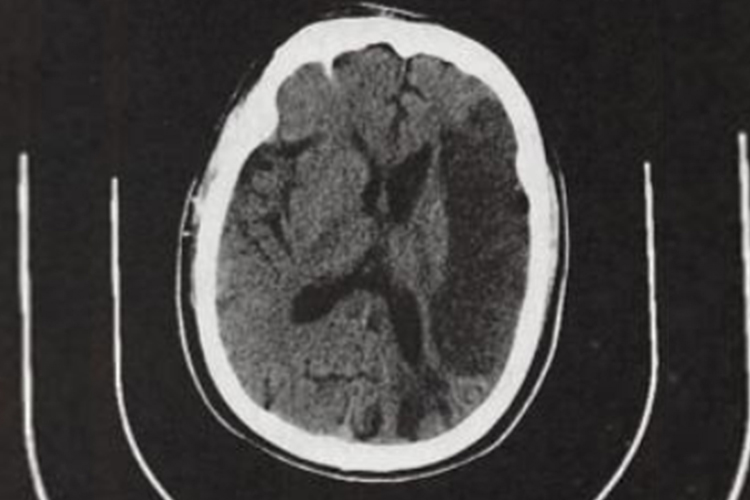

多数患者发病24小时后脑CT逐渐显示低密度梗死灶,发病后2-15日可见均匀片状或楔形的明显低密度灶。MRI可清晰显示早期缺血性梗死,梗死灶T1呈低信号、T2呈高信号。